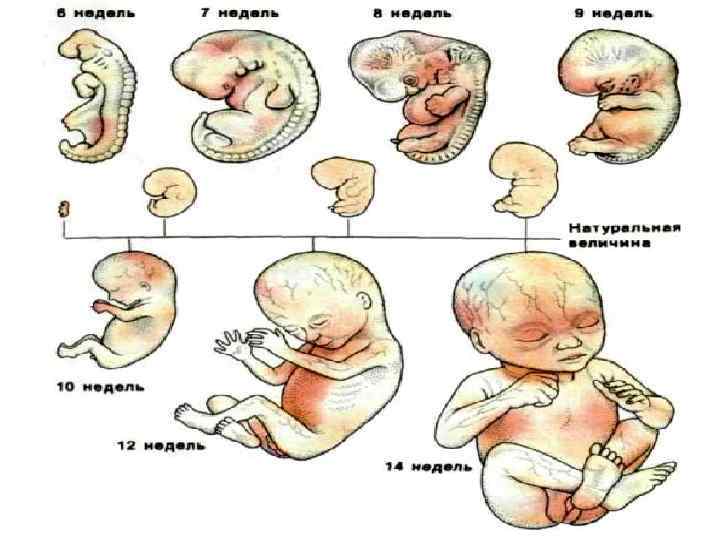

Этапы развития эмбриона человека: 14 недель